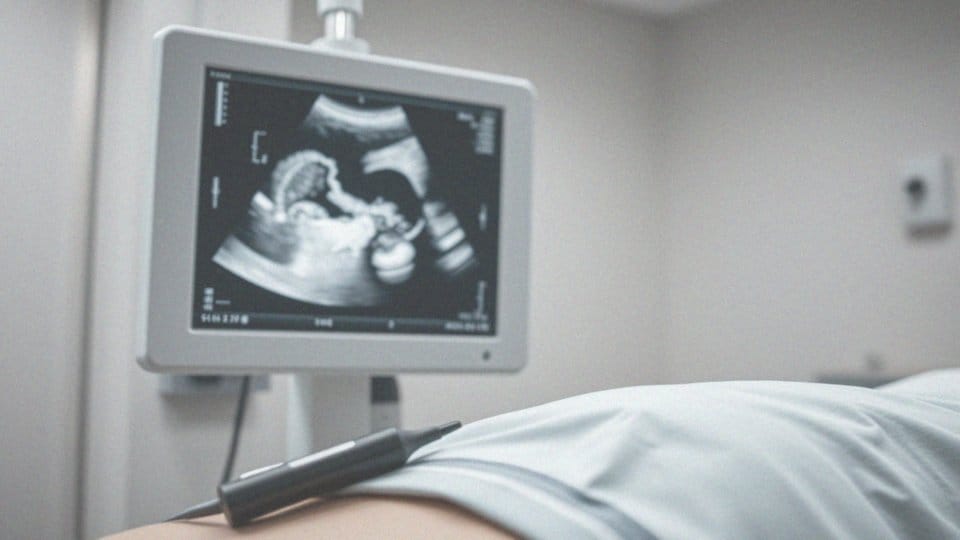

Istotnym elementem tego procesu jest ultrasonografia (USG narządów moszny), która pozwala ocenić:

- rozmiar,

- położenie,

- charakter torbieli.

Co ważne, USG jest metodą nieinwazyjną, dostarczającą cennych informacji o innych potencjalnych problemach, jak:

- guzy,

- stany zapalne.

Jest to badanie dostępne w gabinetach urologicznych i nie wymaga od pacjenta specjalnego przygotowania. Przeprowadzenie USG jest kluczowe dla wykluczenia poważniejszych schorzeń, w tym nowotworów. Ponadto, wyniki tego badania mogą skutkować zaleceniem dodatkowych obrazowych badań, takich jak:

Kiedy pojawia się torbiel jądra lub torbiel nasienna, niezbędne staje się przeprowadzenie kilku kluczowych badań diagnostycznych. Najważniejszym z nich jest ultrasonografia (USG) narządów moszny, które jest nieinwazyjnym sposobem na ocenę torbieli, ich rozmiaru oraz lokalizacji. Wyniki tego badania pozwalają także wykryć potencjalne nowotwory oraz inne schorzenia.